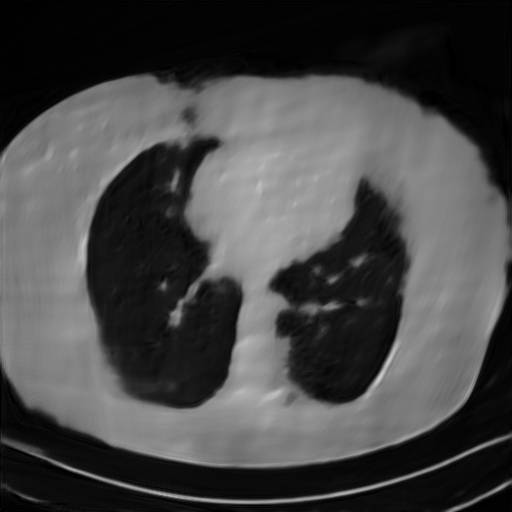

Fig. 4 presents the reconstruction results and residual images obtained by different methods for limited-angle reconstruction. As can be seen, the learning-based methods outperform the direct method and TV model, which exhibit serious artifacts in the missing angle region. Although the denoiser introduced by the FBP-Unet can somehow deal with the noises, the result still presents obvious artifacts. Compared to the SIPID, PD-net and FSR-nets, our LRIP-net1/2 can better preserve the image details and edges with less information left in the residual images. Thus, both the quantitative and qualitative results confirm that the low-to-high double-resolution strategy can improve the reconstruction accuracy for the limited-angle reconstruction problem.

We observe that the low-resolution image prior plays an important role in our method. More specifically, we compare the results of our LRIP-net with respect to different low-resolution priors, which are obtained by down-sampling rate of 1/2, 1/4, and 1/8, respectively. As can be seen in Table III, the best reconstruction results are obtained with the image prior reconstructed by the down-sampling rate of for 150∘, 120∘ and 90∘ limited-angle reconstruction. The visual comparison based on different image priors are also provided in Fig. 5, where obviously less artifacts are left in the reconstruction image by LRIP-net1/8. By comparing the running time, it is easy to see that the smaller the low-resolution image prior, the faster the LRIP-net works.